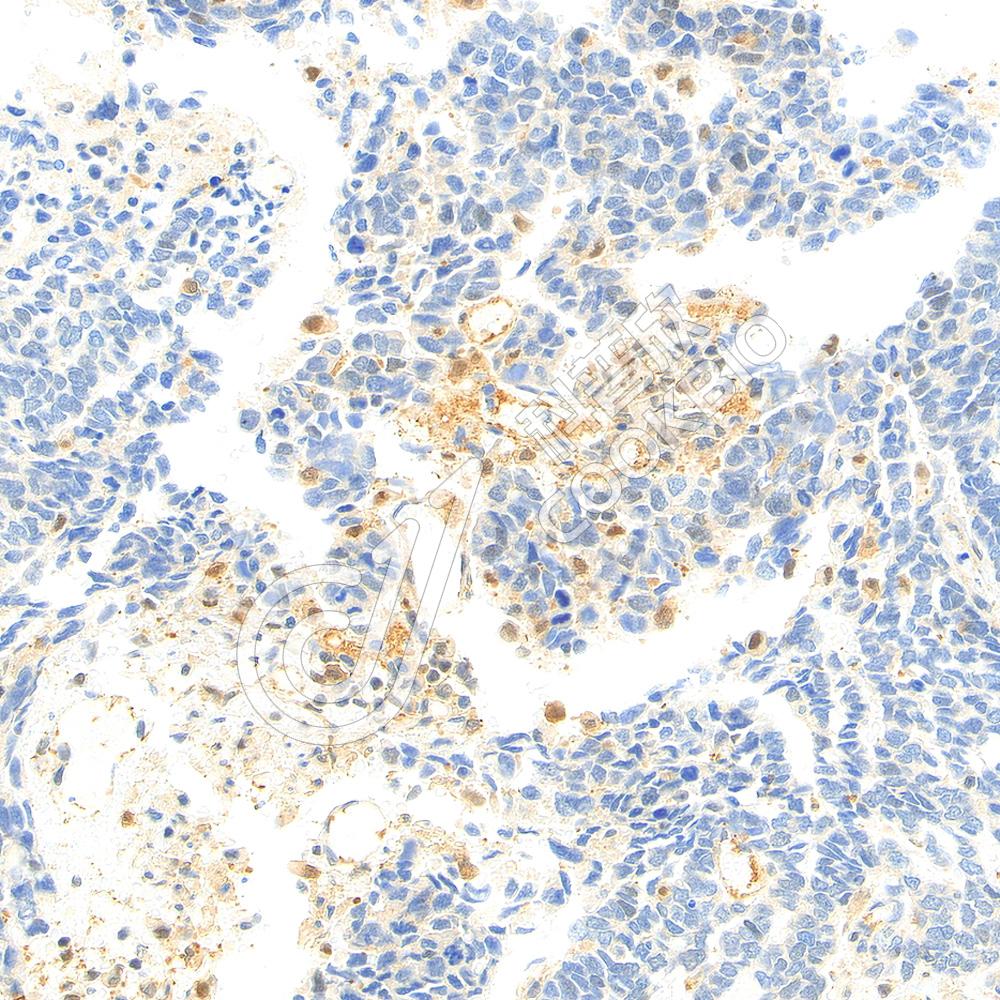

IHC检测HIF-1 alpha蛋白(货号 K5454017).

样品: 人食管癌, 4%多聚甲醛 (货号KSG1101) 固定12-24小时.

抗原修复: Tris-EDTA抗原修复液(pH 9.0) (KSG1203), 98℃, 20分钟.

—抗: 1: 900稀释, 4℃ 孵育过夜.

二抗: S-vision免疫组化多聚二抗(山羊抗兔),即用型 (货号KB3906), 室温孵育20分钟.